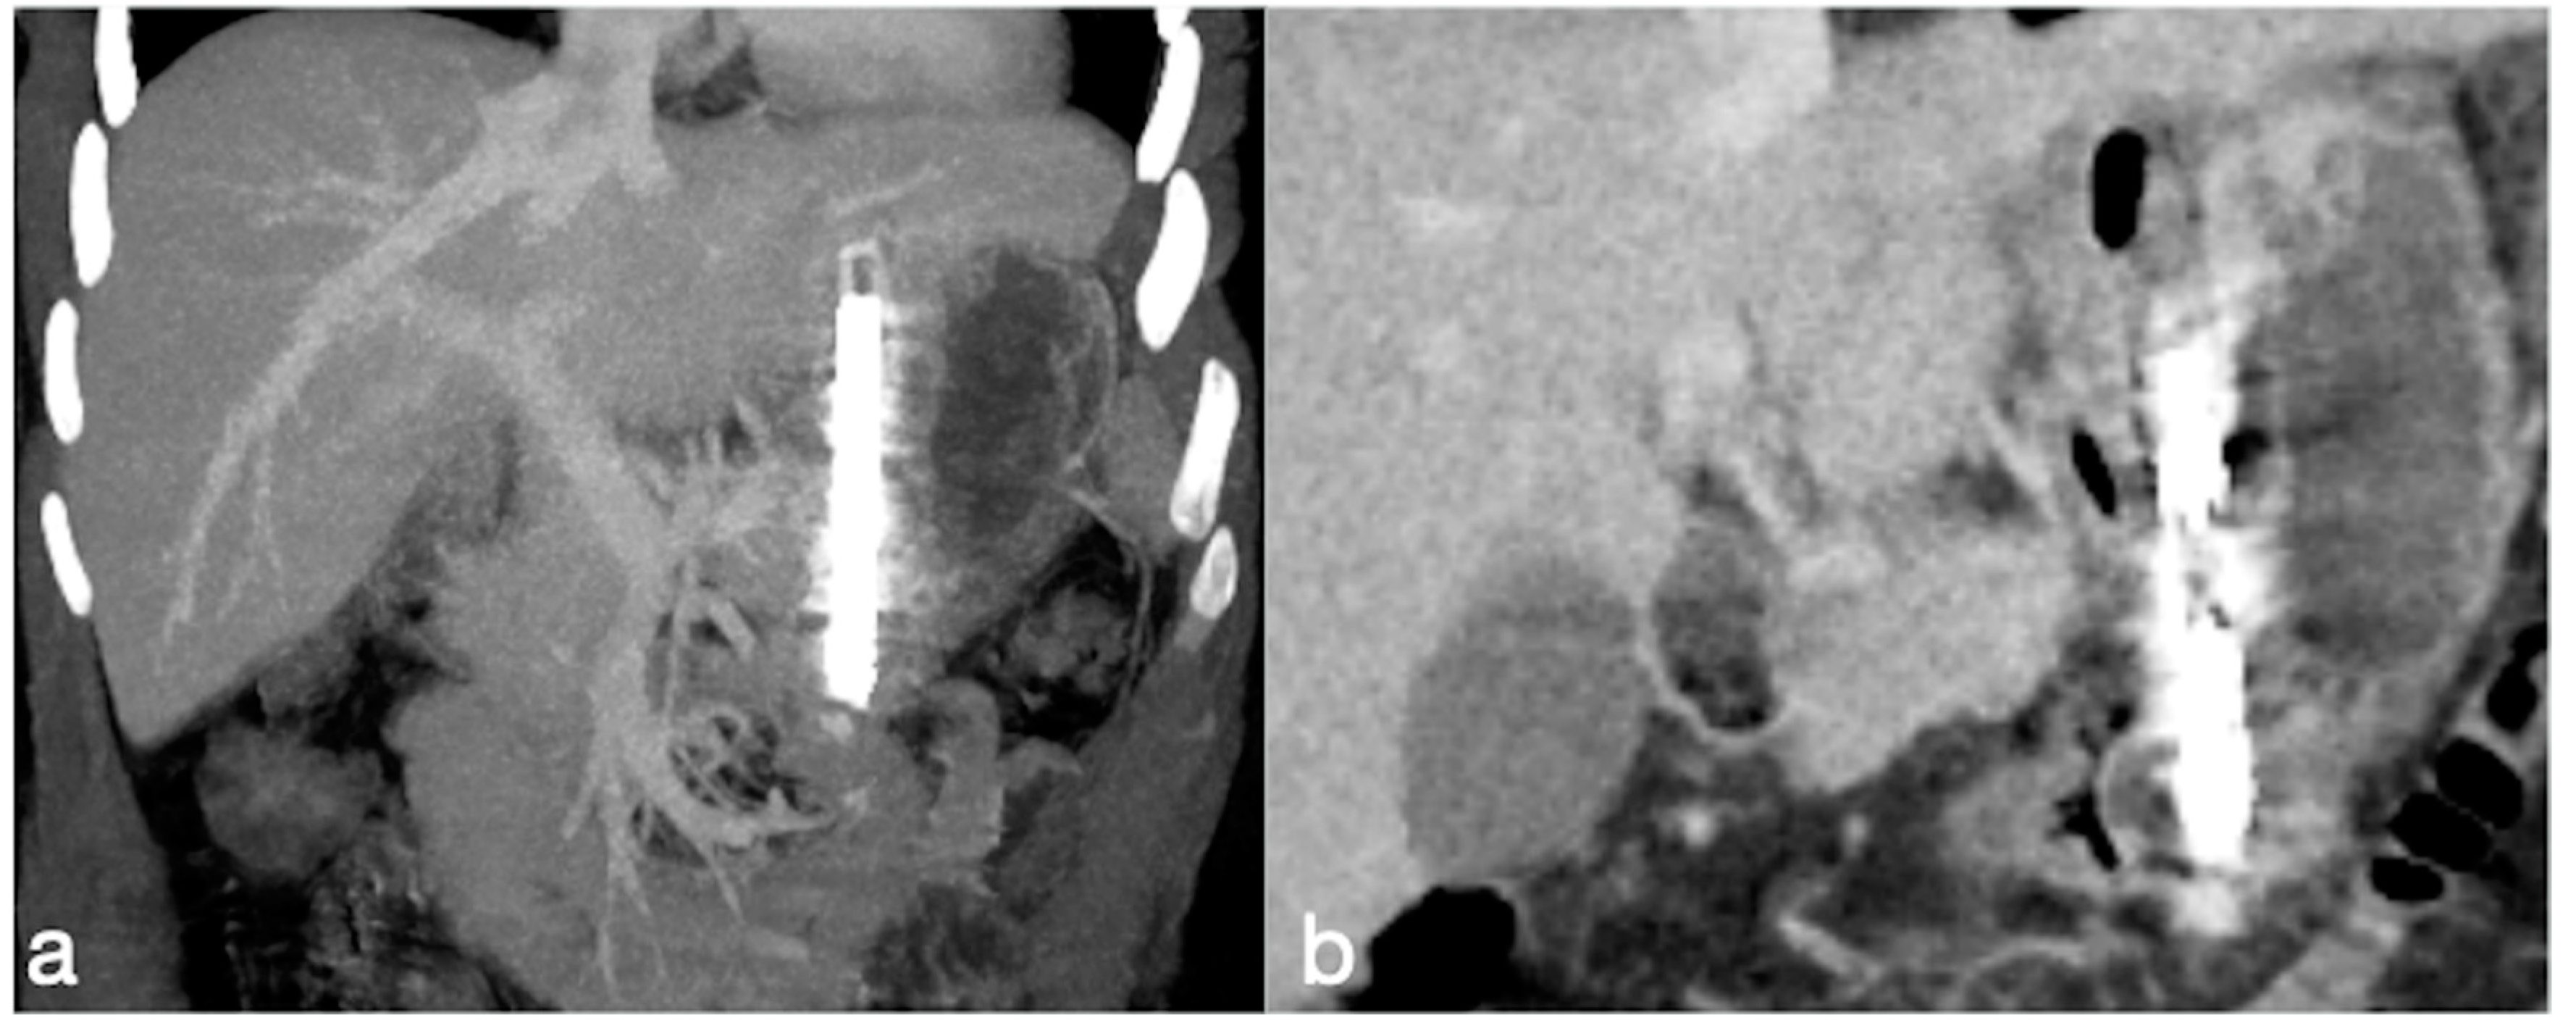

Figure 4. A correct positioning of BariClip® seen at CT coronal MIP (a) and MPR (b) views.

CP procedure reproduces the effect of the sleeve gastrectomy with the advantage of the reversibility by clipping and not cutting the stomach. By using a laparoscopic approach, the BariClip® is placed into the peritoneal cavity. The BariClip is then closed around the stomach parallel to the lesser curvature, creating a small medial pouch and an excluding large lateral segment (Figure 4). To prevent slippage, the BariClip® is sutured to the gastric wall both anteriorly and posteriorly at various levels of the stomach [15].